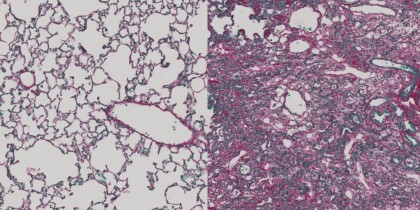

foto: Țesutul pulmonar sănătos conține multe alveole umplute cu aer, în care oxigenul este absorbit din aerul respirator în sânge (stânga). În țesutul pulmonar fibrotic, aceștia au fost înlocuiți de creșteri de țesut conjunctiv (dreapta). (Imagine: Christian Stockmann, UZH)

Folosind imunoterapia, cercetătorii au reușit să reducă fibroza din organele vitale, precum plămâni și ficat, fără a influența funcționarea altor organe și fără a afecta țesuturile sănătoase din vecinătate. Noua abordare se diferențiază de cele încercate anterior întocmai prin capacitatea sa de a ținti doar fibroblastele active, fără a afecta organe sau țesuturi sănătoase, fără fibroză. Potrivit autorilor, au reușit acest lucru în urma analizelor efectuate pe computer, care au arătat că fragmentele a două proteine (Adam12 și Gli1) sunt prezente în număr mare pe fibroblastele activate, însă nu și pe celulele aflate în repaus.

Folosind cele două proteine identificate, cercetătorii au dezvoltat o imunoterapie menită să declanșeze un răspuns imun prin intermediul celulelor imunitare T citotoxice, responsabile în general pentru eliminarea din organism celulelor canceroase sau infectate cu un virus. „Folosind imunoterapia nou dezvoltată, am reușit să eliminăm fibroblastele active la rozătoare, ceea ce a condus la reducerea semnificativă a fibrozei la nivel hepatic și pulmonar, fără a afecta țesutul sănătos al organelor”, concluzionează Stockmann.